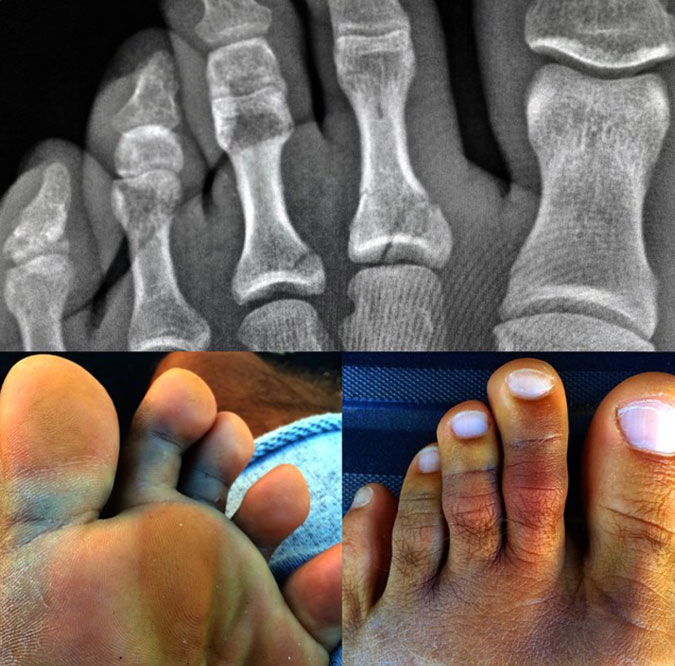

Kelly Slater’s left foot has seen better days. But by December 8, Slater says this left foot will be healed up and leading him out of barrels at Pipe Masters. Photo: @kellyslater

Earlier today we reported that Kelly Slater had injured himself while surfing at Cloudbreak over the weekend. Slater confirmed via Instagram that he broke his second and third toes and sprained three or four toes on his left foot. According to Slater, the injury will require about three weeks in a walking boot along with rehab, but he claims he’ll be ready to rock when the Billabong Pipeline Masters waiting period kicks off on December 8, 2014.

The foamball from the lip landing inside the barrel bounced back up and flipped the board into my foot, hyper-extending the toes backwards. My second toe was sitting kind of across my third one so I knew something was a little off. The worst thing about it was how good the surf was and having to watch from the sidelines afterwards. At least the boys scored a few before the wind went bad and swell backed off. The day before that I went over the falls and broke my fin off with my knee so I’m actually probably lucky to not have gotten hurt worse. Good time to reflect and cleanse the body after two weeks of bacon and barrels at Tavarua.